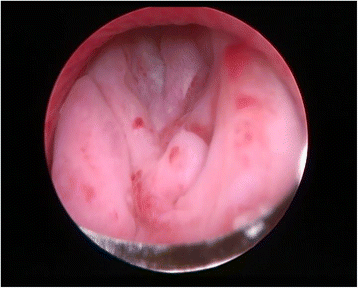

The current report presents the case of a 42-year-old male with extraordinarily salient urination difficulty that had lasted 6 months. Transrectal ultrasonography and pelvic magnetic resonance imaging demonstrated prostatic hyperplasia and cyst. PSA level was 20.65 (>4) μg/L in the patient. Transrectal prostatic biopsy revealed benign prostatic hyperplasia. He agreed to receive plasmakinetic resection of the prostate. During operation a lobulated lump was unexpectedly found on the verumontanum, with the prostate macroscopically normal. Complete tumor excision was performed and pathological assessment indicated phyllodes tumor of the verumontanum. The patient had an uneventful post-operative course and recovered well. The diagnosis, histological classification, treatment, and prognosis of this case are presented. It is necessary to perform cystoscopy to exclude verumontanum tumor even when all imaging examinations indicate prostate hyperplasia, especially in young males. Virtual slides: The virtual slide(s) for this article can be found here: http://www.diagnosticpathology.diagnomx.eu/vs/1868931661161758.